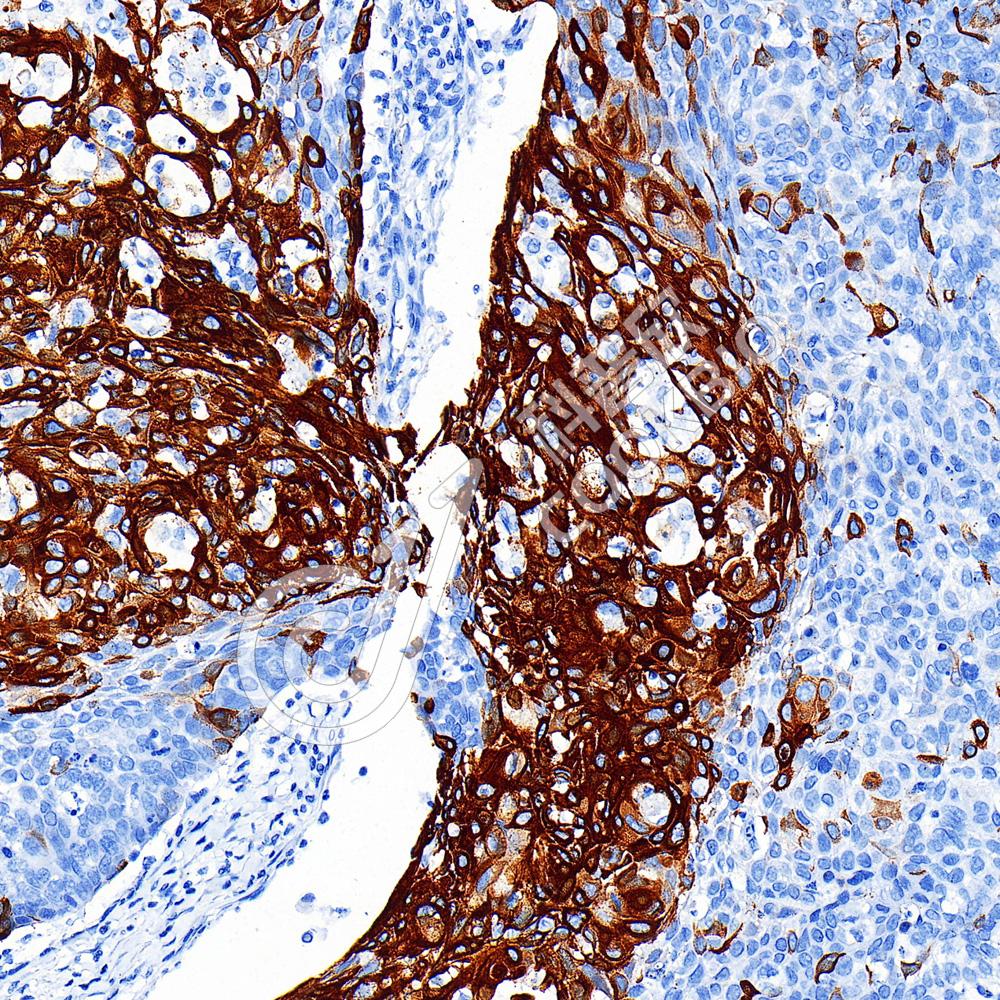

IHC检测Cytokeratin 17蛋白(货号 K5450183).

样品: 人食管癌, 4%多聚甲醛 (货号KSG1101) 固定12-24小时.

抗原修复: 柠檬酸抗原修复液(干粉, pH 6.0) (KSG1201), 高压锅均匀喷气计时2分钟.

—抗: 1: 2000稀释, 4℃ 孵育过夜.

二抗: S-vision免疫组化多聚二抗(山羊抗小鼠), 即用型(货号KB3903), 室温孵育20分钟.